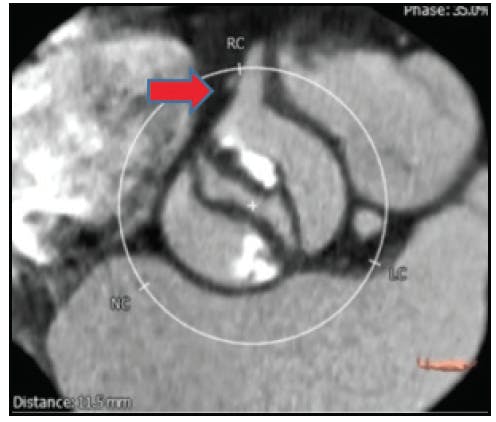

Heavy, asymmetric calcification patterns are also a particular concern in bicuspid valve disease. Heavy calcification may result in incomplete or asymmetric valve expansion and root injury, which can occur due to a contrecoup injury with balloon inflation and THV expansion (Figure 3). Balloon aortic valvuloplasty may be useful in this setting to judge the response of the calcified BAV anatomy before THV implantation. Self-expanding or mechanically expandable THV designs may also be advantageous, although further research on optimal THV selection is required. Unlike tricuspid aortic valves in which both coronary artery ostia are in the middle of the sinuses, in BAV anatomy, one or both ostia may be in proximity to the commissures (Figure 4). This, along with taller leaflet height and heavier calcification, may increase the risk of coronary obstruction, which also remains incompletely understood.

Figure 4. Coronary ostium in close proximity to the commissure in BAV. In this bicuspid valve, the coronary ostium lies in close proximity to the commissure. When combined with longer or bulkier leaflets, this may contribute to a risk of coronary obstruction.